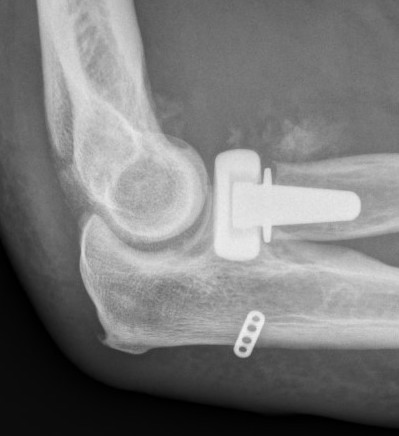

Medartis radial head and neck plating system

Acumed coronoid plating system

Universal posterior approach with radial head replacement and medial approach with medial buttress plate